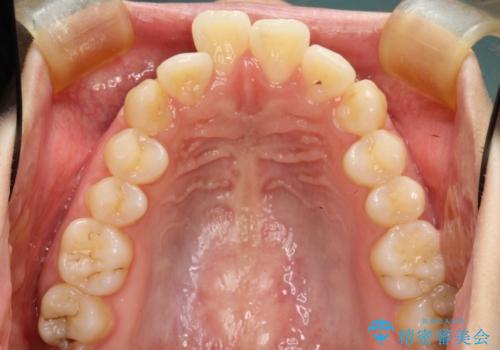

- 口元の突出感を気にして来院された患者様です。

上下左右の第一小臼歯4本を抜歯して口元を下げる治療計画としました。

目立たない装置が希望であったため、上顎が裏側装置である、ハーフリンガル装置を選択されました。